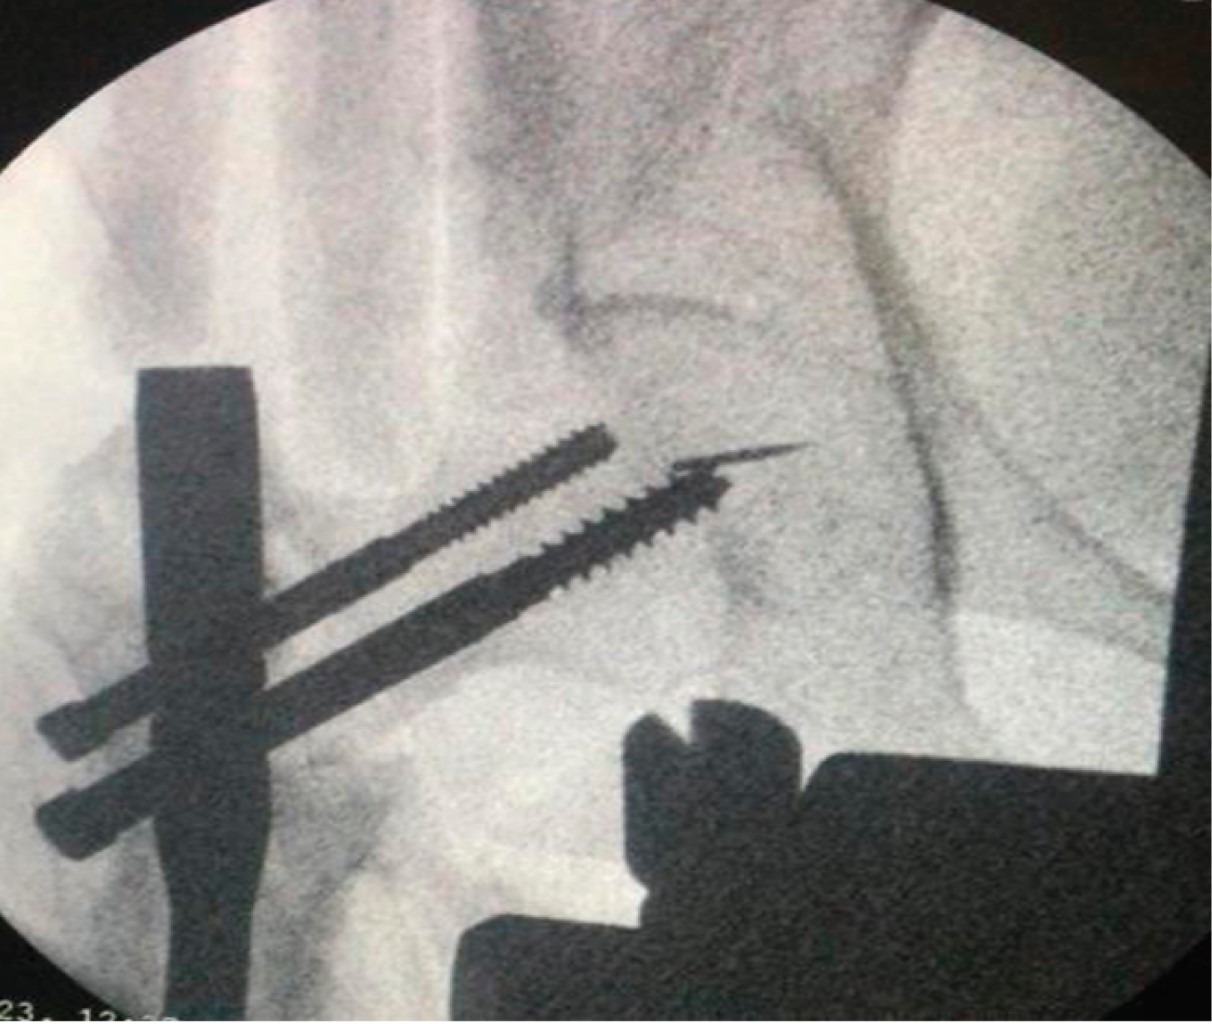

Implant related complications like screw back out (Figure 1), guide wire breakage (Figures 2 and 3), Z effect (Figure 4), TAD outliers (Figure 5) were more in PFN group whereas lateral screw protrusion, locking mechanism failure and barrel disengagement was more in PFNA2 group as shown in Figures 6, 7, 8 and 9. Neck shaft valgus outliers are more common in PFN group (Figure 10).

Nikoloski et al recommended a tip apex distance (TAD) of 20-30mm for PFNA2,25 observing a higher incidence of cut-through when TAD was more than 30 mm or less than 20 mm. In our study, TAD outliers (< 20 or > 30) were 9 and 11 in the PFN and PFNA2 groups, respectively, with a higher implant failure rate, which is consistent with the study by Sharma et al, who had more outliers in the PFNA2 group but fewer implant failures.26 Our results, supporting the study by Sharma et al., indicate that achieving an optimal TAD is crucial, but some outliers are acceptable in the PFNA2 group (as shown in Figure 5), likely due to its inherent stability.

According to the Cleveland index, maintaining an optimal position (centre-centre, inferior-centre) of the screw is crucial for a good outcome.12 Complications were more frequent when the screw position was suboptimal in the PFN group. When the index was centre-centre in both groups, no complications were observed, and outcomes were better, whereas five out of eight screws that were in a suboptimal position backed out. Only one case in the PFN group with an inferior-centre index showed a complication of screw back-out. Our results are consistent with other studies comparing these implant designs. Mora A et al compared PFNA with PFN and found a lower incidence of cut-out with PFNA.27 Choo SK et al found less postoperative sliding with PFNA compared to PFN, like our study, which found no difference in walking capacity between patients with either implant.28